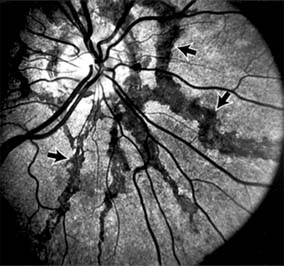

CENTRAL SEROUS CHORIORETINOPATHY

Central serous chorioretinopathy is characterized by serous detachment of the sensory retina as a consequence of focal leakage of fluid from the choriocapillaris through a defect in the retinal pigment epithelium (Figures 10-2 and 10-3). This disease typically affects young to middle-aged men and may be related to life stress events. Most patients present with the sudden onset of blurred vision, micropsia, metamorphopsia, and central scotoma. Visual acuity is often only moderately decreased and may be improved to near-normal with a small hyperopic correction.

Figure 10-2

Figure 10-2: Central serous chorioretinopathy with sensory retinal detachment (arrows) extending into the fovea.

Figure 10-3

Figure 10-3: Fluorescein angiogram of central serous chorioretinopathy shows active disease with both a retinal pigment epithelial detachment (small arrows) and a sensory retinal detachment (large arrows). Two foci of inactive disease (open arrows) are also present.

The diagnosis is made by slitlamp examination of the fundus; the presence of serous detachment of the sensory retina in the absence of ocular inflammation, subretinal neovascularization, an optic pit, or a choroidal tumor is diagnostic. The retinal pigment epithelial lesion appears as a small, round or oval, yellowish-gray spot that is variable in size and may be difficult to detect without the aid of fluorescein angiography. Fluorescein dye leaking from the choriocapillaris may accumulate below the pigment epithelium or sensory retina, resulting in a variety of patterns including the well-recognized smokestack configuration.